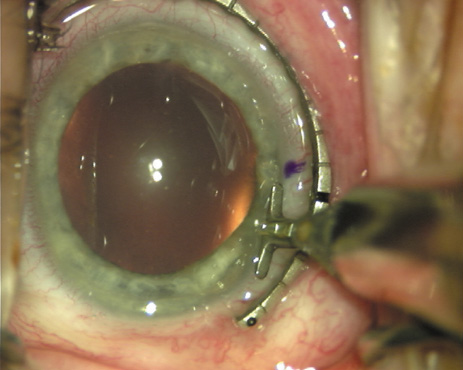

Case 1 is a 68-year-old male who presented for right cataract surgery. His refraction was −1.00 +2.25 × 80 and was recorded as reliable, consistent with his modest cataract density. Keratometry readings were 44.75 × 75 and 43.00 × 165. Corneal topography confirmed slightly more than 2.00 D of regular and slightly oblique cylinder. Consulting the nomogram, a plan was devised for a pair of LRIs to be centered over the 75-degree axis, with each incision delineating 45 degrees of arc. A single plane phaco incision was used and maintained at a size of less than 3.2 mm (Figs. 811).

Fig. 8. Steep meridian is confirmed intraoperatively by keratoscopy. In this left eye viewed from the temporal side, the “short axis” of the corneal mire is seen to be at the 75-degree meridian. (Reprinted from Hardten DR, Lindstrom RL, Davis EA. Phakic Intraocular Lenses: Principles and Practice. Thorofare, NJ: SLACK Incorporated, 2004, with permission.)

Fig. 9. The broad hash marks of the fixation ring/gauge are centered over the 75-degree meridian, using the 6:00 limbal mark for orientation. Alternatively, a Mendez gauge may be used. (Reprinted from Hardten DR, Lindstrom RL, Davis EA. Phakic Intraocular Lenses: Principles and Practice. Thorofare, NJ: SLACK Incorporated, 2004, with permission.)